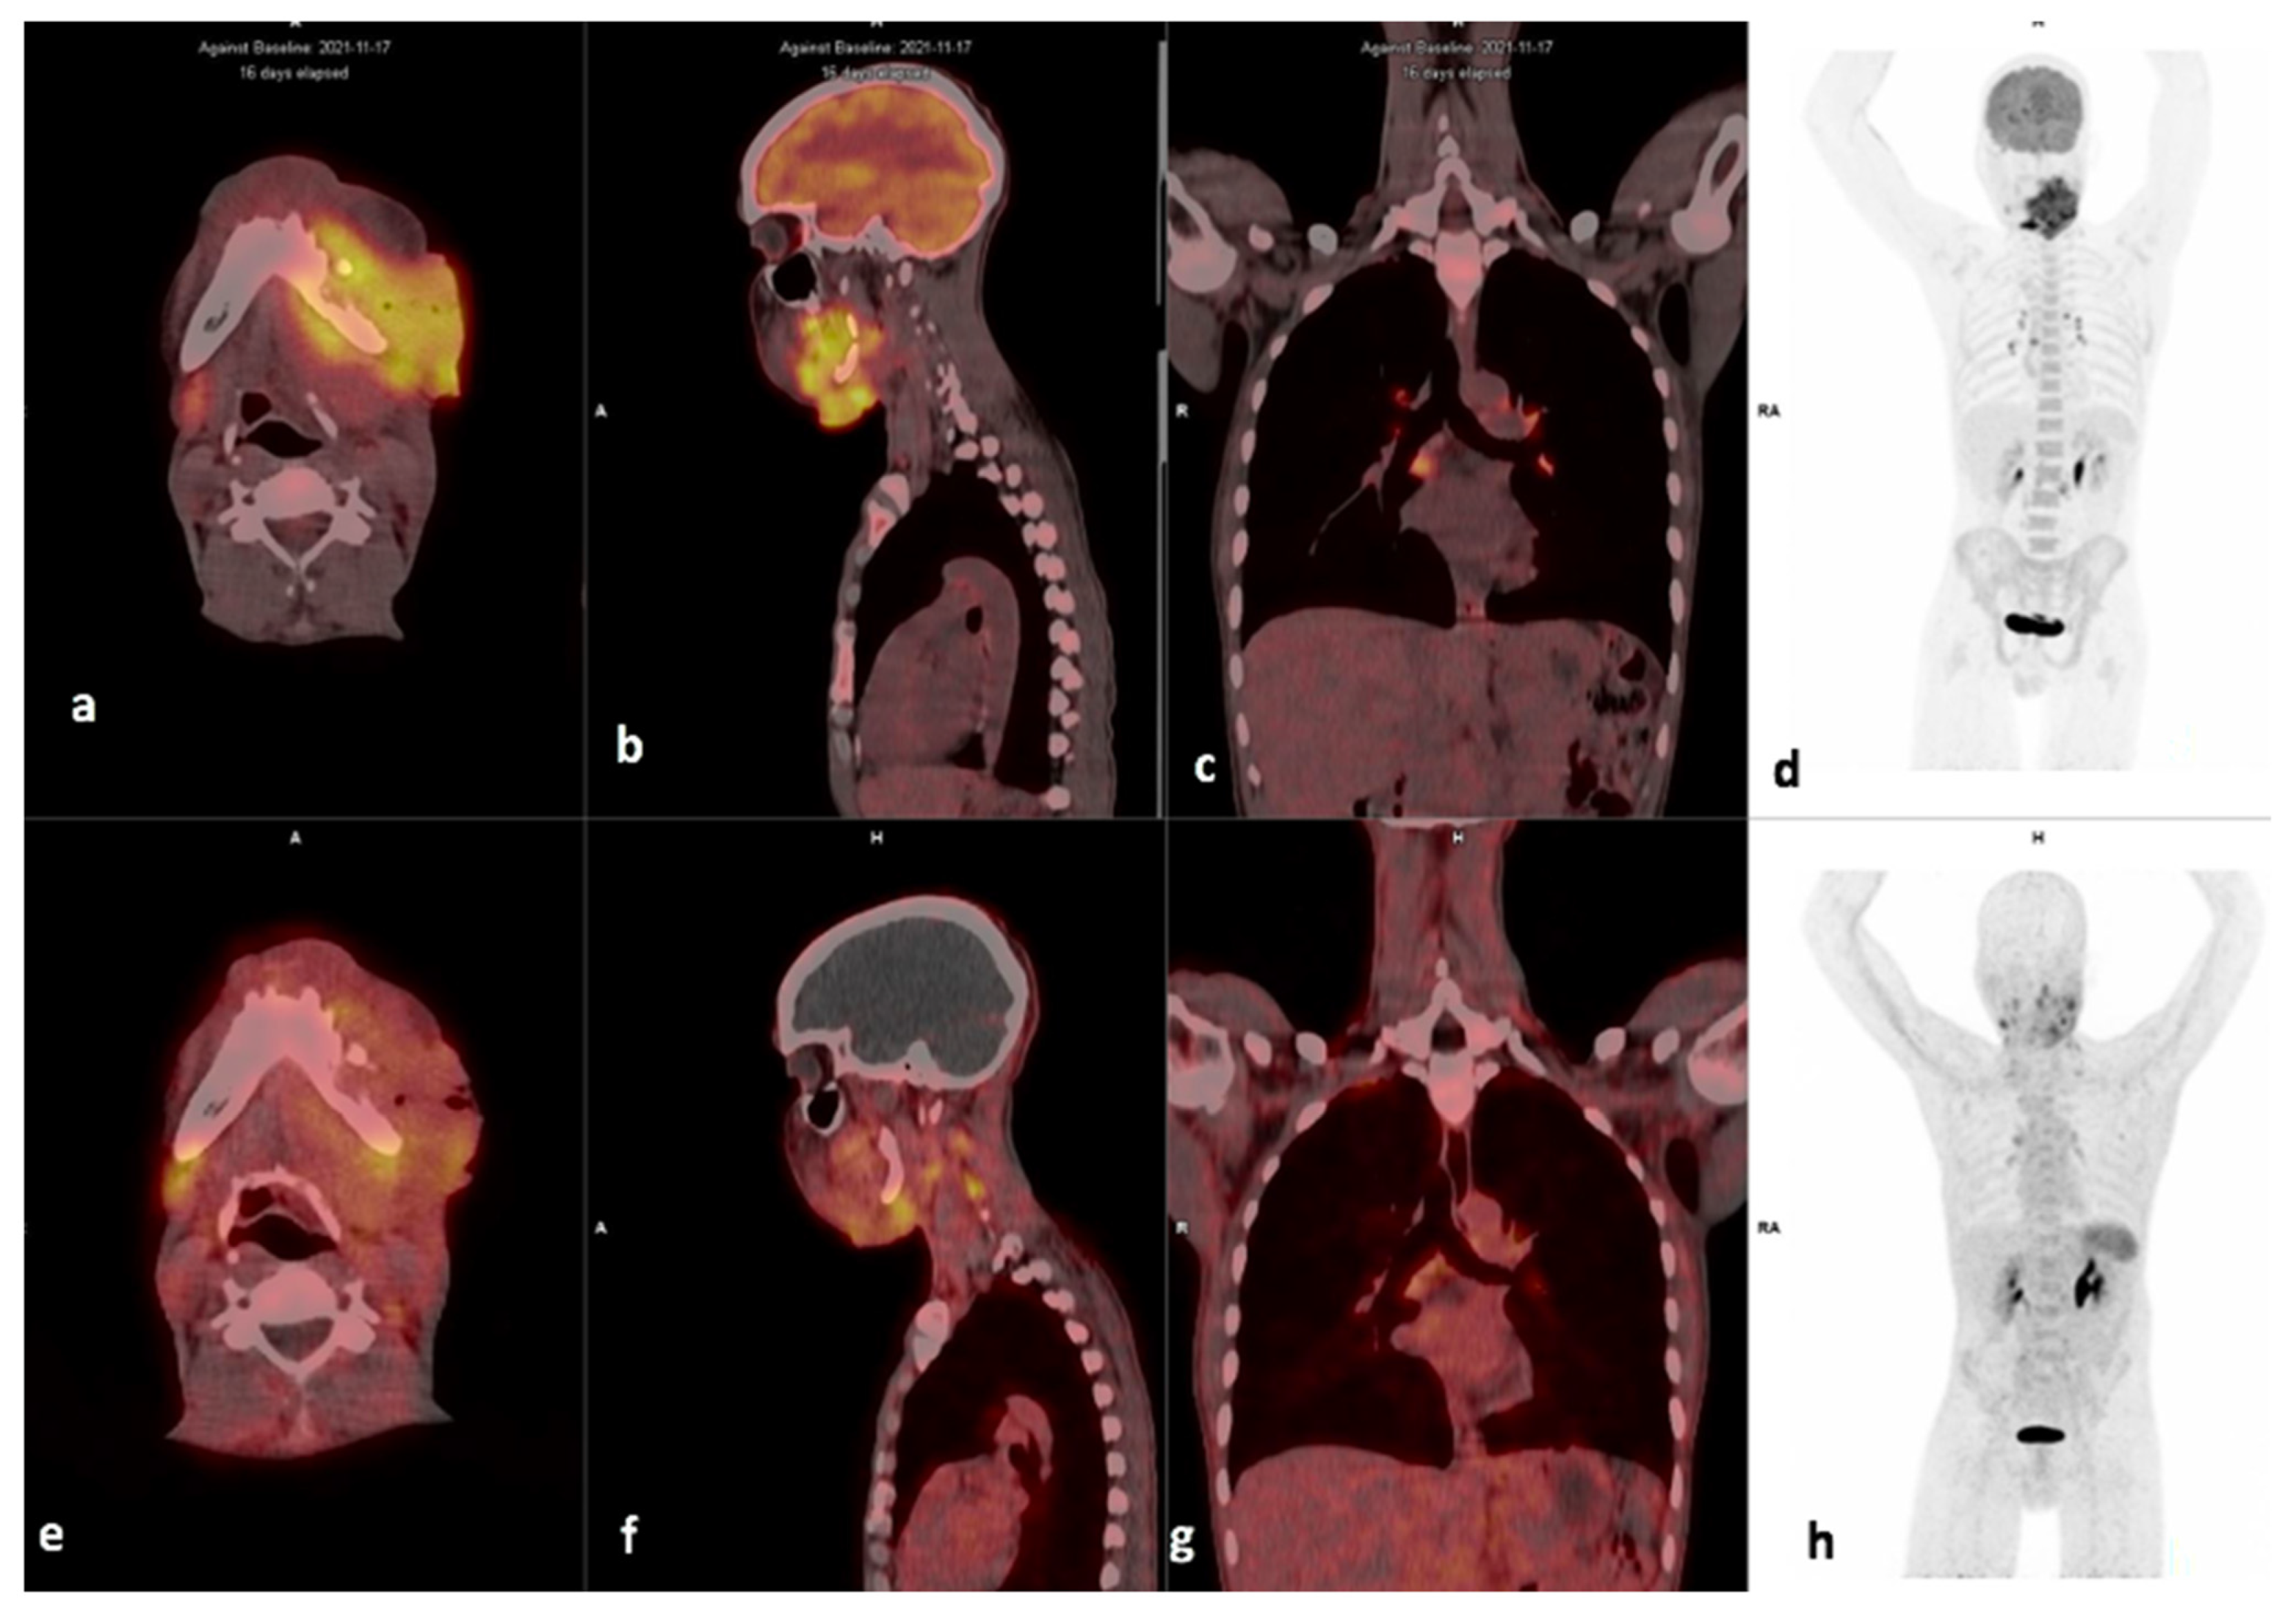

3.3. Visual Analysis